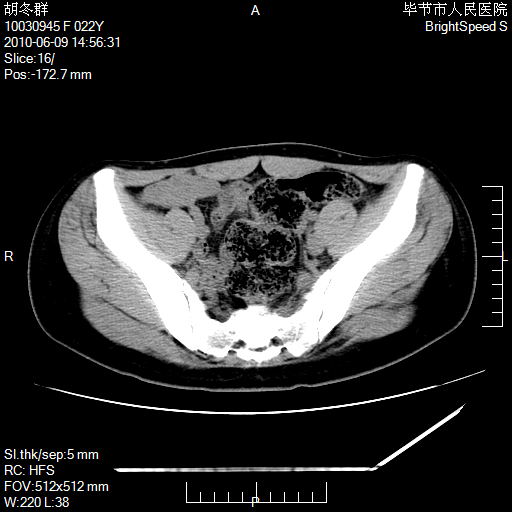

患者23岁,发现腹部包块3月。

左侧卵巢囊腺瘤或囊腺癌

盆腔内囊性占位性病变;考虑左侧卵巢囊腺瘤。

有分隔、壁薄,支持考虑左侧卵巢囊腺瘤。

左侧卵巢浆液性囊腺瘤。

支持考虑左侧卵巢囊腺瘤;宫腔积液。

有分隔、壁薄,支持考虑左侧卵巢囊腺瘤。排尿后,膀胱缩小,由于重力作用,肿块下移就到了膀胱位置,很好理解。